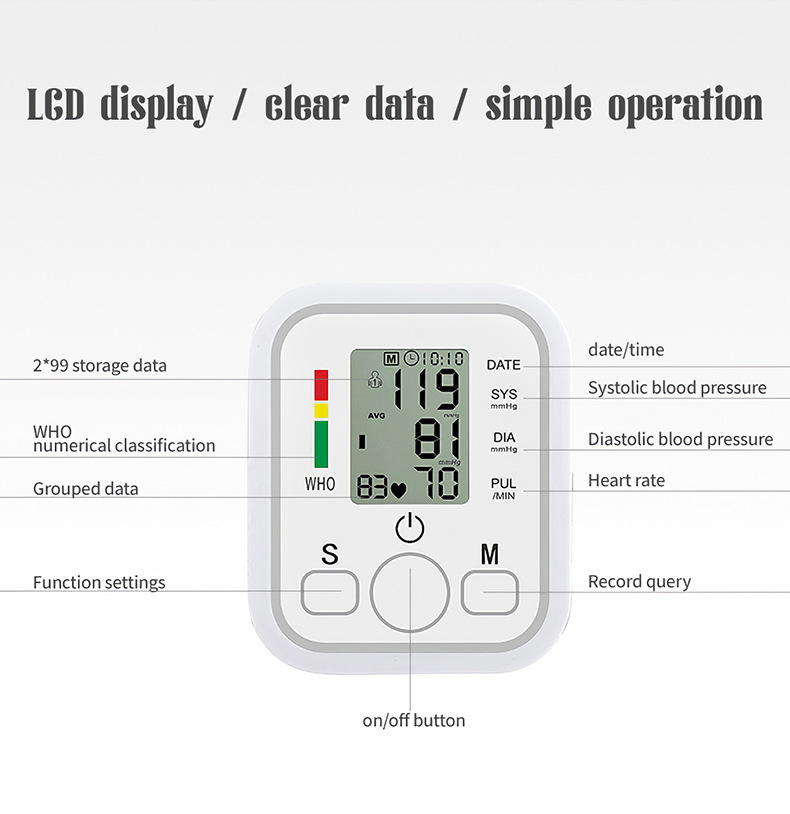

Product Image: